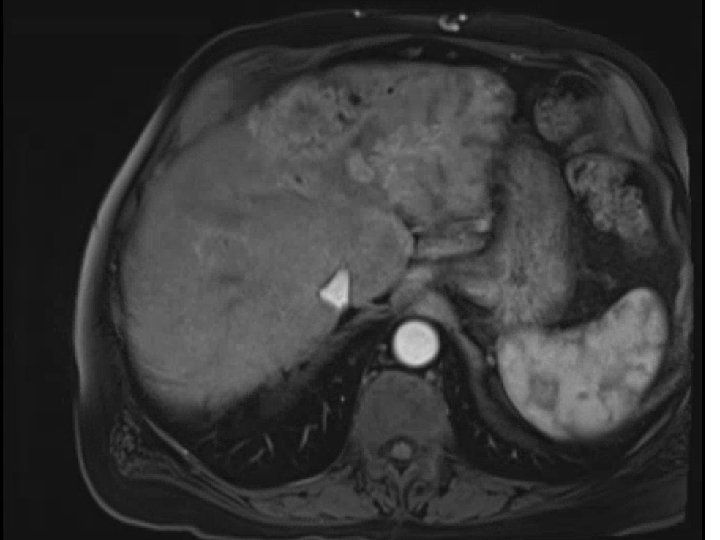

• 74 y. o. male with a large left lobe HCC involving Segment

• 74 y. o. male with a large left lobe HCC involving Segment II, III, and IV also with left portal vein thrombosis. Biopsy confirmed at OSH as moderately differentiated HCC. BCLC stage C tumor. Child-Pugh A with an ECOG PS of 0. Patient presented to MGH for consideration of radioembolization. Patient did not desire chemotherapy due to significant side-effects

Pre-presentation MRI

Pre-SIRT